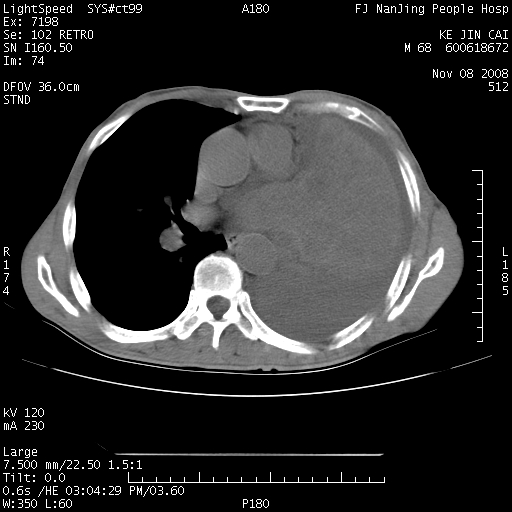

是个很有看头的病例,咋人气那么不旺?没多少人兴趣呢?这个病例几大怪:1   恶性肿瘤侵犯心肌左房怪,心肌一般不会被恶性肿瘤侵犯吧?2   左下肺均匀实变怪,内无含气,有别一般不张实变,含气肺泡完全为液体取代,而非一般不张实变的肺萎陷,冷不丁还以为是肿大的脾脏3   肿瘤本身怪,像tb肺不张4   这么有看头的病例没人气怪。呵呵。

追查病史,咳嗽,患者无发热,血象不高。据说2年前胸片检查怀疑肺ca曾行纤支镜检查,病理未见到癌细胞。无确切资料。

左肺恶性肿瘤侵犯肺动脉,左心房内瘤栓,胸膜转移。